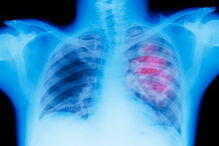

Cancro do pulmão é o que mais mata em Portugal.

O relatório do Programa Nacional para as Doenças Oncológicas 2017, que compila dados entre 2011 e 2015, mostra que a incidência das doenças oncológicas regista um aumento de 3% por ano e é considerada a segunda causa de morte, depois das doenças cérebro-cardiovasculares. Entre os cancros que mais matam está o do pulmão, com um "aumento significativo" nas mulheres.

Ainda segundo o relatório, a seguir ao cancro do pulmão, os do cólon e do reto são os que mais pessoas matam em Portugal. A faixa etária com maior incidência de casos é a partir dos 60 anos.

Nuno Miranda – Continua a ser o do pulmão, com mais de 4 mil óbitos em 2015. Houve um aumento significativo de incidência no sexo feminino. No entanto, sabemos que é um cancro evitável. Se pensarmos que 90% dos casos estão relacionados com o consumo de tabaco, percebemos que que temos de investir na prevenção.